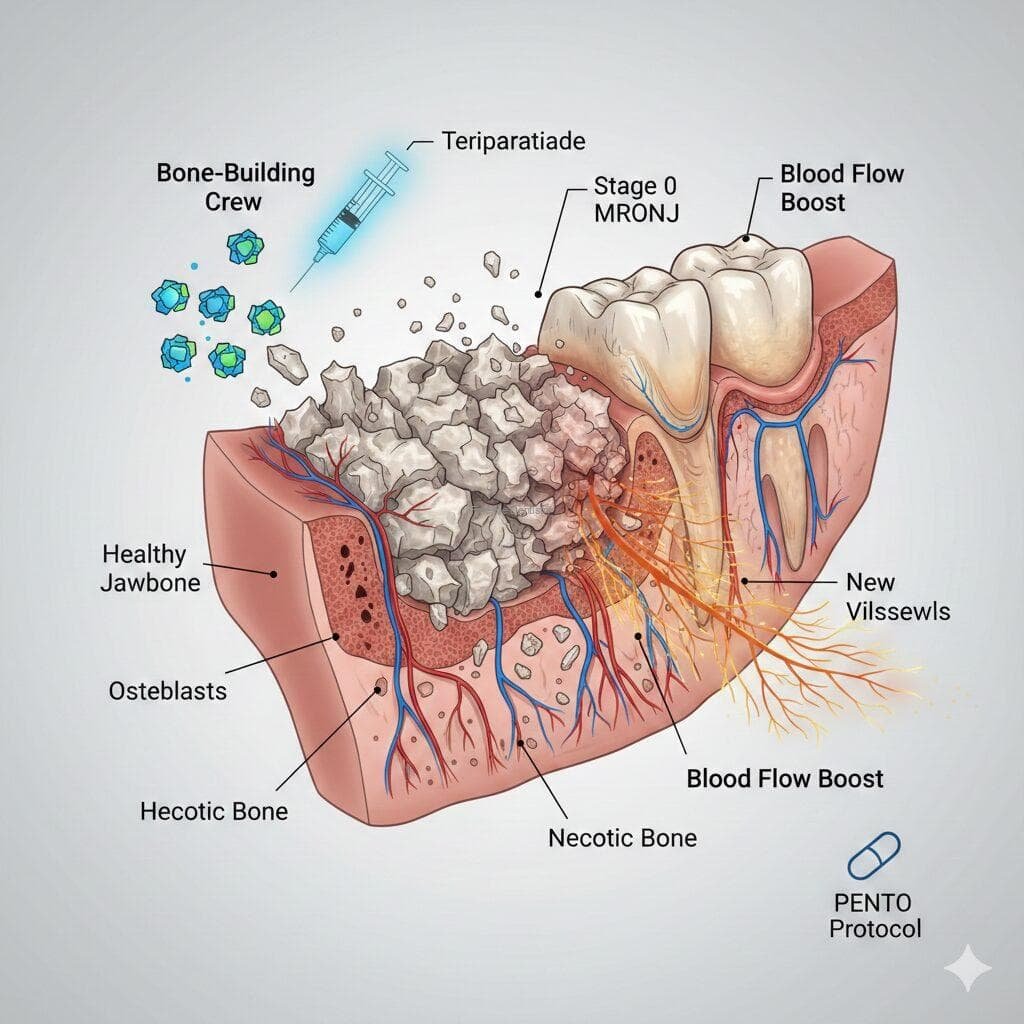

MRONJ stands for Medication-Related Osteonecrosis of the Jaw. It is a condition where an area of the jawbone fails to heal and remains “exposed” (you can see or feel the bone through your gums) for more than 8 weeks.

- The Benefit: A CBCT (3D Dental Scan) allows surgeons to see inside the bone. The Italian guidelines emphasize that internal bone changes on a CT scan can confirm a diagnosis even if the bone isn’t visible through the gums yet (referred to as Stage 0).

- The “Bone Builder” (Teriparatide/Forteo): The 2025 Korean Consensus confirms this is a game-changer for osteoporosis patients. It acts like a “new crew of workers” (osteoblasts) that build fresh bone. This “Self-Healing Effect” can sometimes push out dead bone on its own, helping you avoid major surgery.

- For Cancer Patients (PENTO Protocol): Since Forteo isn’t usually recommended for cancer patients, doctors use the PENTO Protocol (Pentoxifylline and Vitamin E). This “softens” scarred tissue and brings fresh blood supply back to the jawbone.

- The Future (Evenity/Romosozumab): The newest “kid on the block” in 2026 research. It is the most powerful bone-builder available and is being studied to provide an even faster “jumpstart” than Teriparatide.